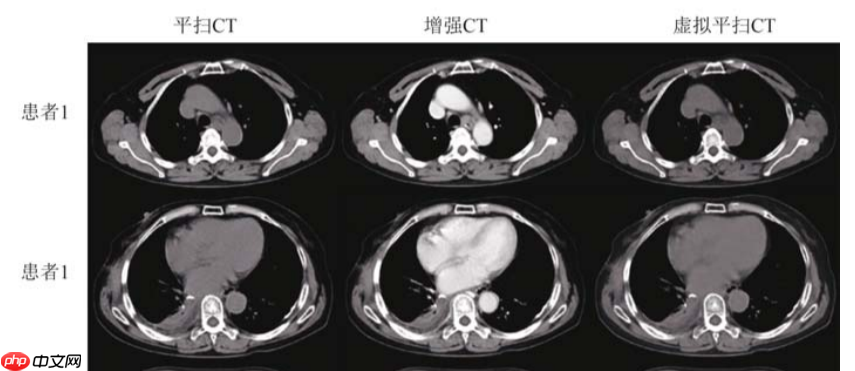

【1】文章使用Unet对增强CT数据进行训练,最终预测生成对应的虚拟平扫CT图像,达到只需要对患者扫描一次CT即可,避免患者接受过多的放射辐射。